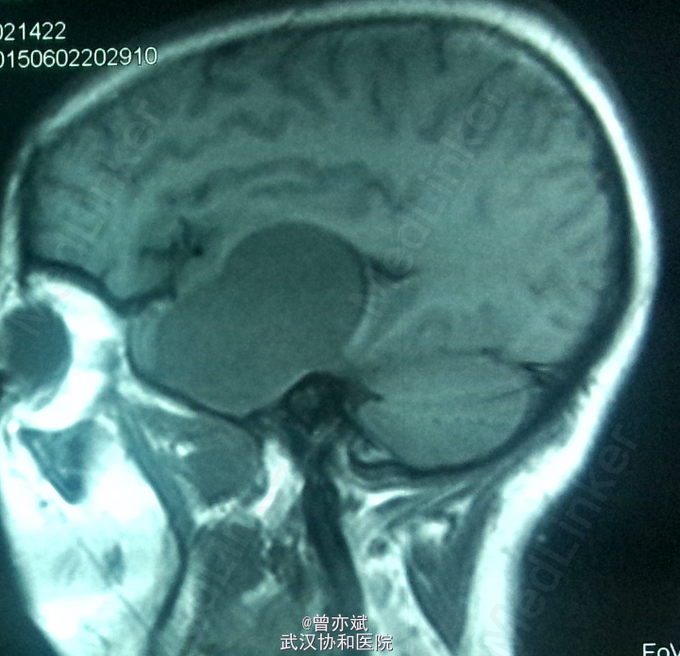

主诉:左眼视力下降十余年 简要现病史:患者10余年前出现左眼视力下降,当时未在意,近期右眼视力下降,行CT提示颅内占位。

查体:左眼视力0.8 颞侧偏盲,右眼视力 0.5 余无明显阳性体征。既往无特殊。 MRI: 稍长 T1,高flair信号,增强明显强化 ,其内点片状强化减低区。诊断:鞍区、中颅窝底巨大占位,考虑脑膜瘤可能性大。

从 MRI上看,矢状位 增强可疑脑膜尾征,增强虽然明显但 不均匀 ,酷似脑膜瘤表现,手术中所见血供丰富,肿瘤实质多为血窦,考虑海绵状血管瘤。如果术前 能 诊断是海绵状血管瘤 ,是开颅手术还是分次伽马刀? 有大神指点一二不?